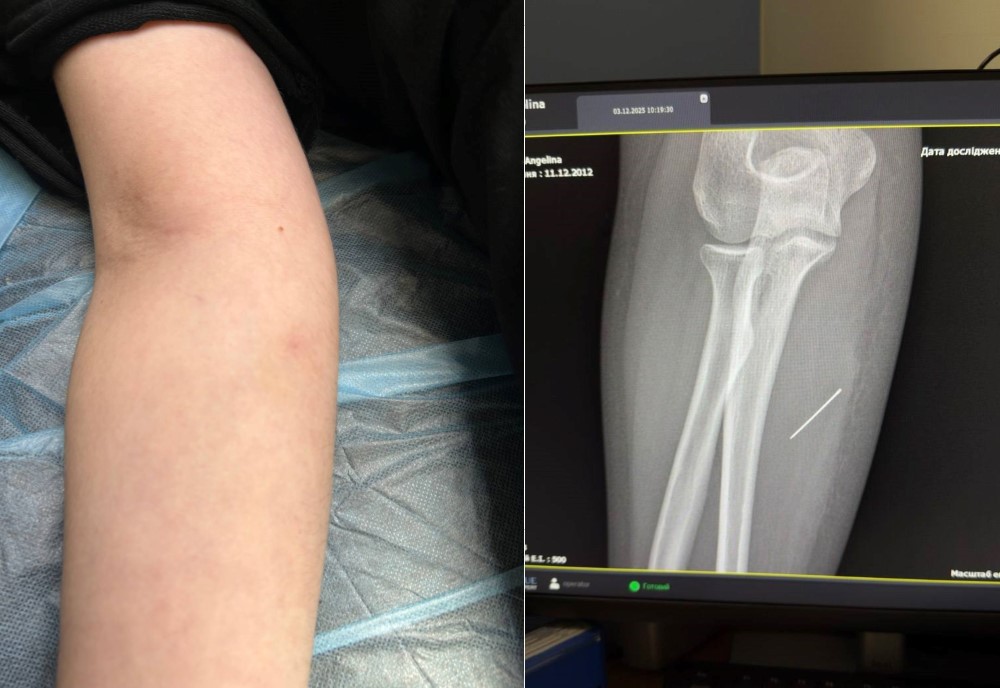

Якось увечері 13-річна Ангеліна з містечка Дубляни шила поробку на урок – новорічну прикрасу. Голки дівчинка залишила на столі. А вранці через відключення світла збиралася до школи у напівтемряві та раптом відчула різкий колючий біль у руці. Батьки під час огляду помітили лише маленьку цятку і подумали, що це укус комахи. Однак вже за кілька днів на місці «укусу» з’явилася набряклість, а рука стала так сильно боліти, що Ангеліна не могла її зігнути. Тож батьки повезли дочку у лікарню.

За той тиждень, що Ангеліна проходила з голкою, та просунулася глибше. Вже на рентгені лікарі чітко побачили, що голка зайшла під кутом 45 градусів і застрягла глибоко в товщі м’яза. Якби вона мігрувала ще далі, то могла б пошкодити або судини, або нервові закінчення.

Під час операції критично важливим було витягнути голку точно за траєкторією її входження, щоб вона не зламалася. Адже пошук дрібних уламків у м’язах є значно важчим завданням. За допомогою рентген-навігації ЕОП хірурги точно визначили місце знаходження стороннього тіла, невеликий розріз та правильно і безпечно його вилучили.